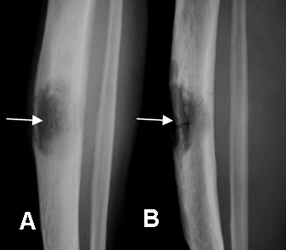

Fig 38. Osteomielitis subaguda.

A: Rx AP y B: Rx lateral. Defecto óseo en la diáfisis tibial, por absceso de brodie.